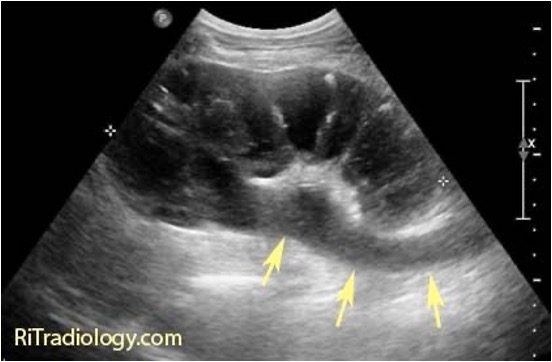

Renal calculus

Calculus are often seen as echogenic focus that is associated with posterior acoustic shadowing.

In addition, if you put color doppler over the echogenic focus, twinkling artifact may be present which supports the diagnosis of renal calculus.